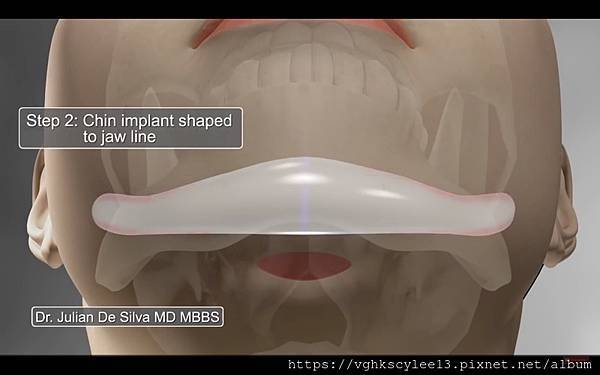

1.假體:假體直接讓下巴骨延伸不動原來骨頭。

(網路截圖)

(以上網路截圖)